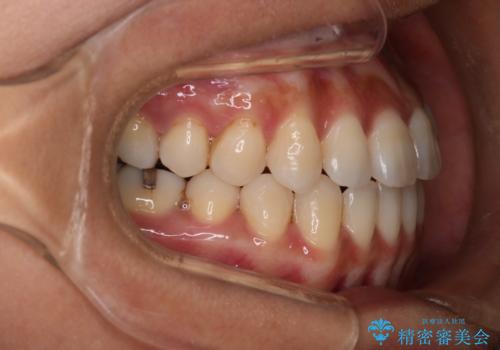

- 開咬を主訴に来院されました。前歯部に開咬、右側大臼歯部にクロスバイトが認められます。ワイヤー矯正の審美装置で治療し、ゴム掛けを行いながら噛み合わせを改善しました。

主訴である開咬と右側大臼歯部クロスバイトを改善でき、しっかりと噛むことができるようになりました。